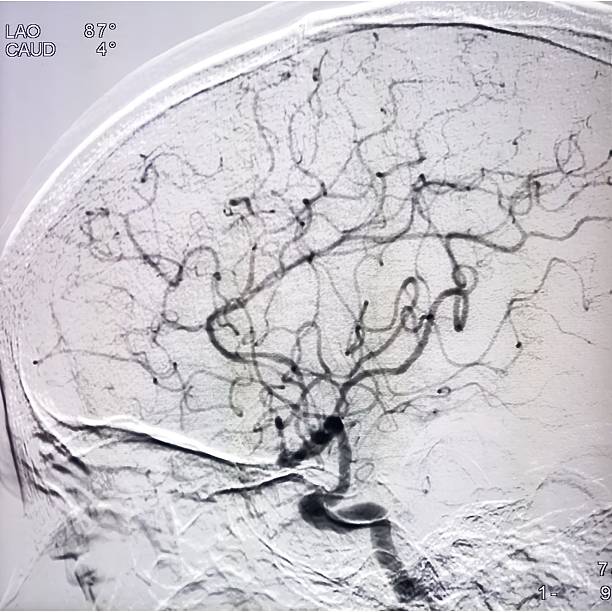

🟢 뇌경색이란 무엇인가요?

뇌경색은 뇌혈관이 막히면서 해당 부위에 혈액이 공급되지 않아 뇌세포가 손상되는 질환이에요.

**‘허혈성 뇌졸중’**이라고도 하며, 전체 뇌졸중의 약 **70~80%**를 차지할 만큼 흔한 형태입니다.

보통은 고혈압, 당뇨, 고지혈증, 흡연, 심장질환 등이 주요 원인으로 작용하죠.